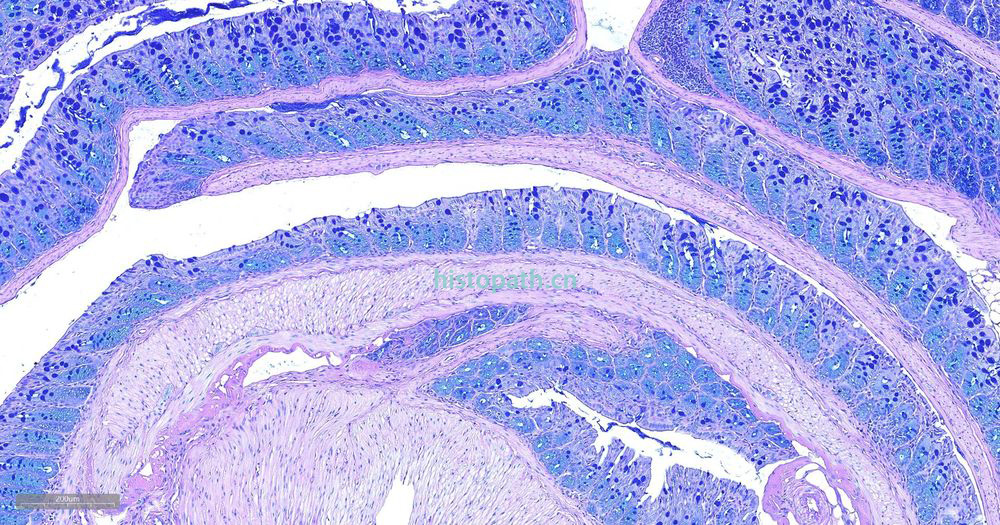

糖原染色是病理学中常规的染色方法之一,该法常用来显示糖原和其他多糖,该染色液不仅能够显示糖原,还能显示中性黏液性物质和某些酸性物质。

阿利新蓝和PAS技术联合使用可鉴别同一组织切片中的中性黏蛋白和酸性黏蛋白。这种技术也常用作广泛检测黏蛋白的手段。阿利新蓝可将唾液黏蛋白、硫黏蛋白和蛋白多糖染成蓝色。PAS技术可将中性黏蛋白染成深红/红紫色,同时将既含中性黏蛋白有含酸性黏蛋白的组织和细胞染成深浅不同的紫色,这是由于阿利新蓝与 Schiff试剂结合并反应。上述染色常可出现在含有中性黏蛋白和唾液黏蛋白的小肠杯状细胞中。

阿利新蓝是类铜钛花青染料,这种阳离子染料与酸性基团结合,也即阿利新蓝与组织内含有的阴离子基团如羧基和硫酸根形成不溶性复合物。分子中带正电荷的盐键与酸性黏蛋白多糖物质中带负电荷的酸性基团结合形成不溶性的复合物而呈蓝色,再与PAS进行复合染色,就能显示三种不同黏液物质成分。